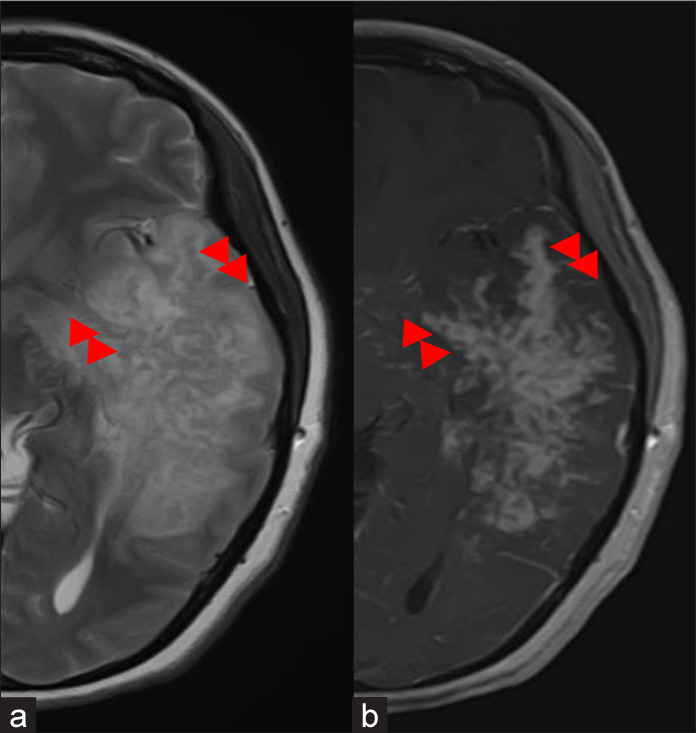

Case description: Herein, we report the presentation of a 34-year-old immunocompetent Pashtun female with acute-onset rapidly progressing generalized weakness, altered cognition, and motor and speech deficits. Although the radiological findings resembled a glioblastoma, the strong clinical suspicion of a fungal infection and her improvement on voriconazole treatment led to the decision to avoid surgical resection, thereby minimizing the risk of potential dissemination.